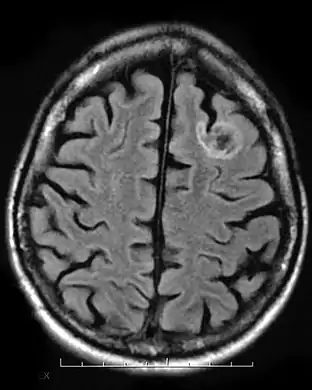

Dysembryoplastic neuroepithelial tumour, MRI FLAIR.

A dysembryoplastic neuroepithelial tumour is commonly diagnosed in patients who are experiencing seizures with magnetic resonance imaging (MRI), electroencephalogram (EEG).[4] A DNT is most commonly diagnosed in children who are experiencing seizures, and when given medication do not respond to them. When an MRI is taken there are lesions located in the temporal parietal region of the brain.[4]

Typical DNTs can be detected in an EEG scan when there are rapid repetitive spikes against a contrasted background.[4] EEG are predominantly localized with DNT location in the brain, however there are nonspecific cases in which the location of the tumour is abnormal and not localized.[4]